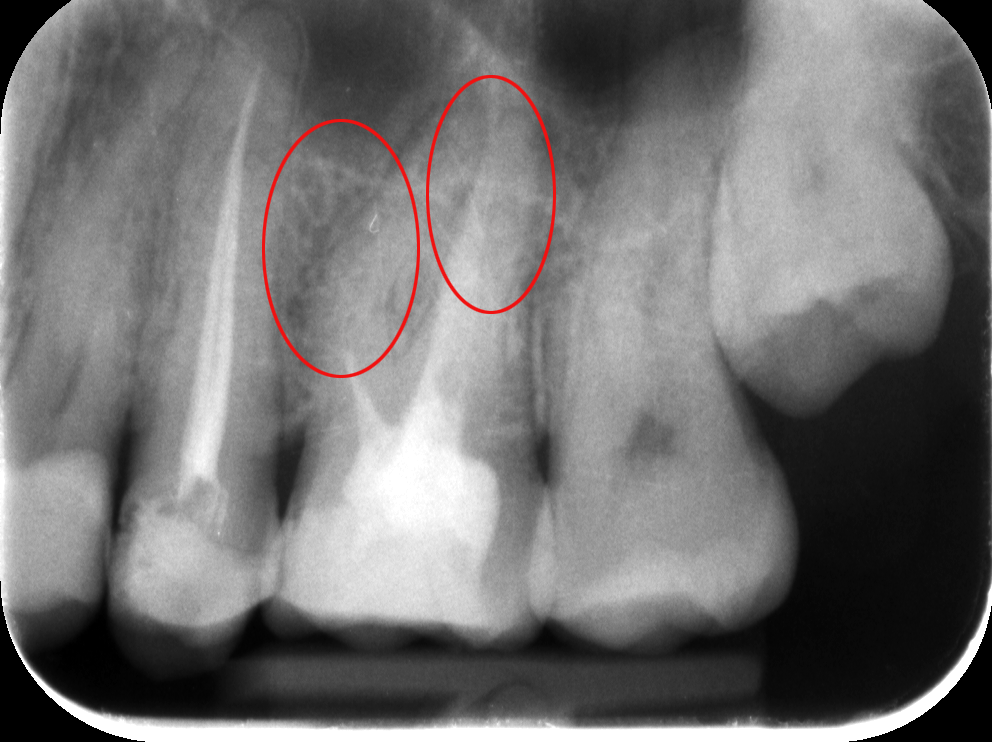

Dr. Molnár Katalin, egyik szakértőnk vizsgálta meg a pácienst. A szájüregi vizsgálatot röntgenfelvétel követte – a diagnózis felállításához és a kezelés menetének felvázolásához mindenképpen szükség van röntgenfelvételre is. A képen látható, hogy egy rosszul elvégzett gyökértömés van az egyik felső 6-osban, amely körül már látható a kezdődő elváltozás. A rossz gyökértömés körül ugyanis könnyen gyulladás alakul ki, amely nemcsak fájdalmas, de meg is változtatja a csontszövet szerkezetét.

Az elkészült röntgenfelvételeken tehát a sötétebb területek jelzik a gyulladás fennállását (pirossal bekarikáztuk), a foggyökércsatornák halványabban látszanak, elmosódottabbak vagy teljesen eltűnnek a felvételen.